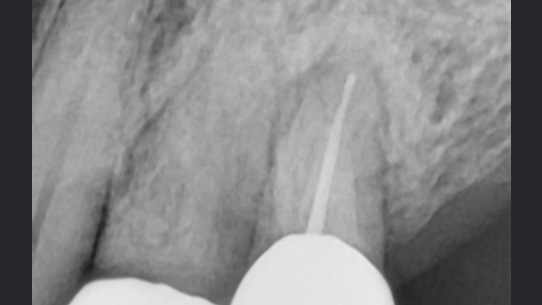

뿌리에 염증으로 흔들리는 치아

치주 치료로 재생된 건강한 잇몸

치주염은 잇몸의 뼈 부분까지 염증이 진행된 상태를 말합니다. 치석이 치주염 상태가 될 때까지, 즉, 치아 뿌리까지 들러붙어 내려가게 되면

치주인대가 소실되고 치조골까지 녹아 내리게 됩니다. 고운미소에서는 임플란트를 하기 전에 치주치료, 큐렛, 근관치료, 치근단 수술,

치아 재식술등의 다양한 치료로 치아를 최대한 살리려고 노력하고 있습니다.